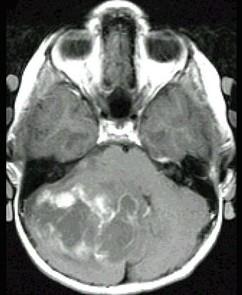

问题 颅后窝肿瘤(如图所示)临床症状应除外()

选项 A.轮替试验幅度增大 B.躯干性和下肢远端的共济失调 C.交叉性麻痹 D.Romberg征多为阴性 E.同侧后组脑神经损伤症状

答案 D